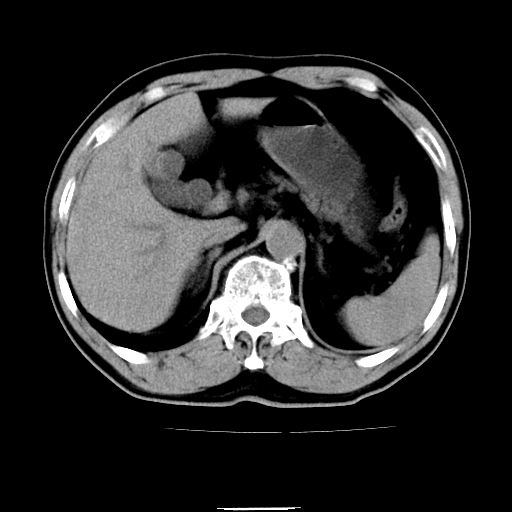

以下是引用chenqiong在2010-3-25 20:56:00的发言:[br]1、胆囊炎,胆囊息肉[br]2、肝内胆管及胆总管扩张,胆总管下端结石[br]3、十二指肠乳头旁憩室

以下是引用zxl51642在2010-3-26 10:47:00的发言:[br]胆囊炎,胆囊息肉,胆总管扩张,但未看到明显肿块,肝内胆管扩张不像恶性,炎性狭窄或阴性结石可能吧,建议mrcp,右肾小囊肿